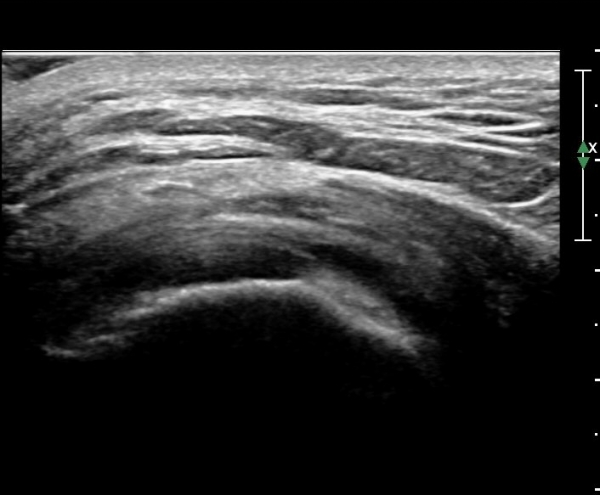

´ëÀüÀÚ µÚÂÊ È¾´Ü¸é°Ë»ç¿¡¼­ ÁߵбÙÈûÁÙ°ú Àå°æÀÎ´ë »çÀÌ¿¡ ·®ÀÇ ¼ö¾×Àú·ù°¡ °üÂûµÇ°í(»çÁø 1)